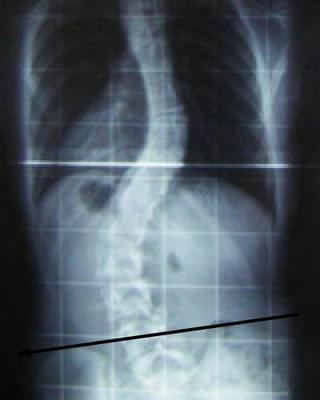

I have a thoracolumbar scoliosis

I developed an idiopathic scoliosis when I was in my 10th grade and now I am 18 years of age. I never experienced any pain at first but now I kind of experience back pains and get tired after standing for long hours.

Most thoraco-lumbar scolioses are caused by a short leg; it's not uncommon, and can usually be corrected by the simple insert of an inner in the shoe.

You may need a STANDING X-ray of your pelvis.